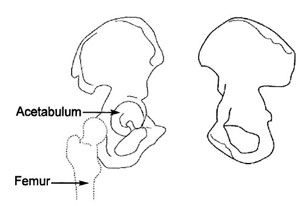

The

Acetabulum refers to the part of the pelvis that meets the upper end of the thigh bone (the femoral head) to form the hip joint. In a healthy hip, these two bones fit together like a ball and cup, in which the ball rotates freely in the cup. Cartilage lines the bones where they meet at the joint and there is little friction between the surfaces during movement.

Anatomical illustration of the acetabulum